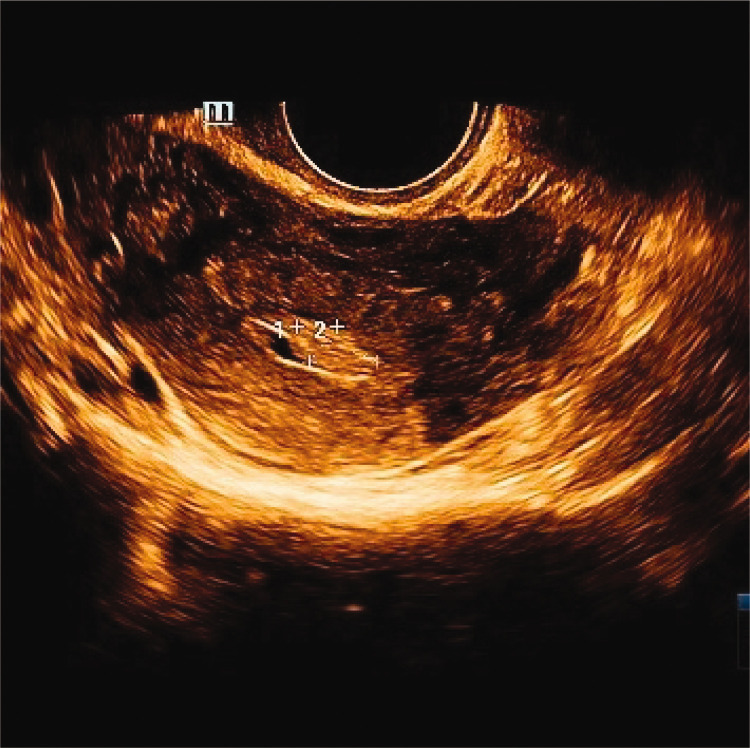

Ovarian hemangioma is an extremely rare benign tumor in clinical practice. We report the case of a postmenopausal woman presenting with vaginal bleeding, in whom imaging revealed a right adnexal mass. Surgical excision of the adnexa was performed, and pathological examination confirmed a right ovarian hemangioma. Concurrent findings included endometrial polyps and cervical polyps.